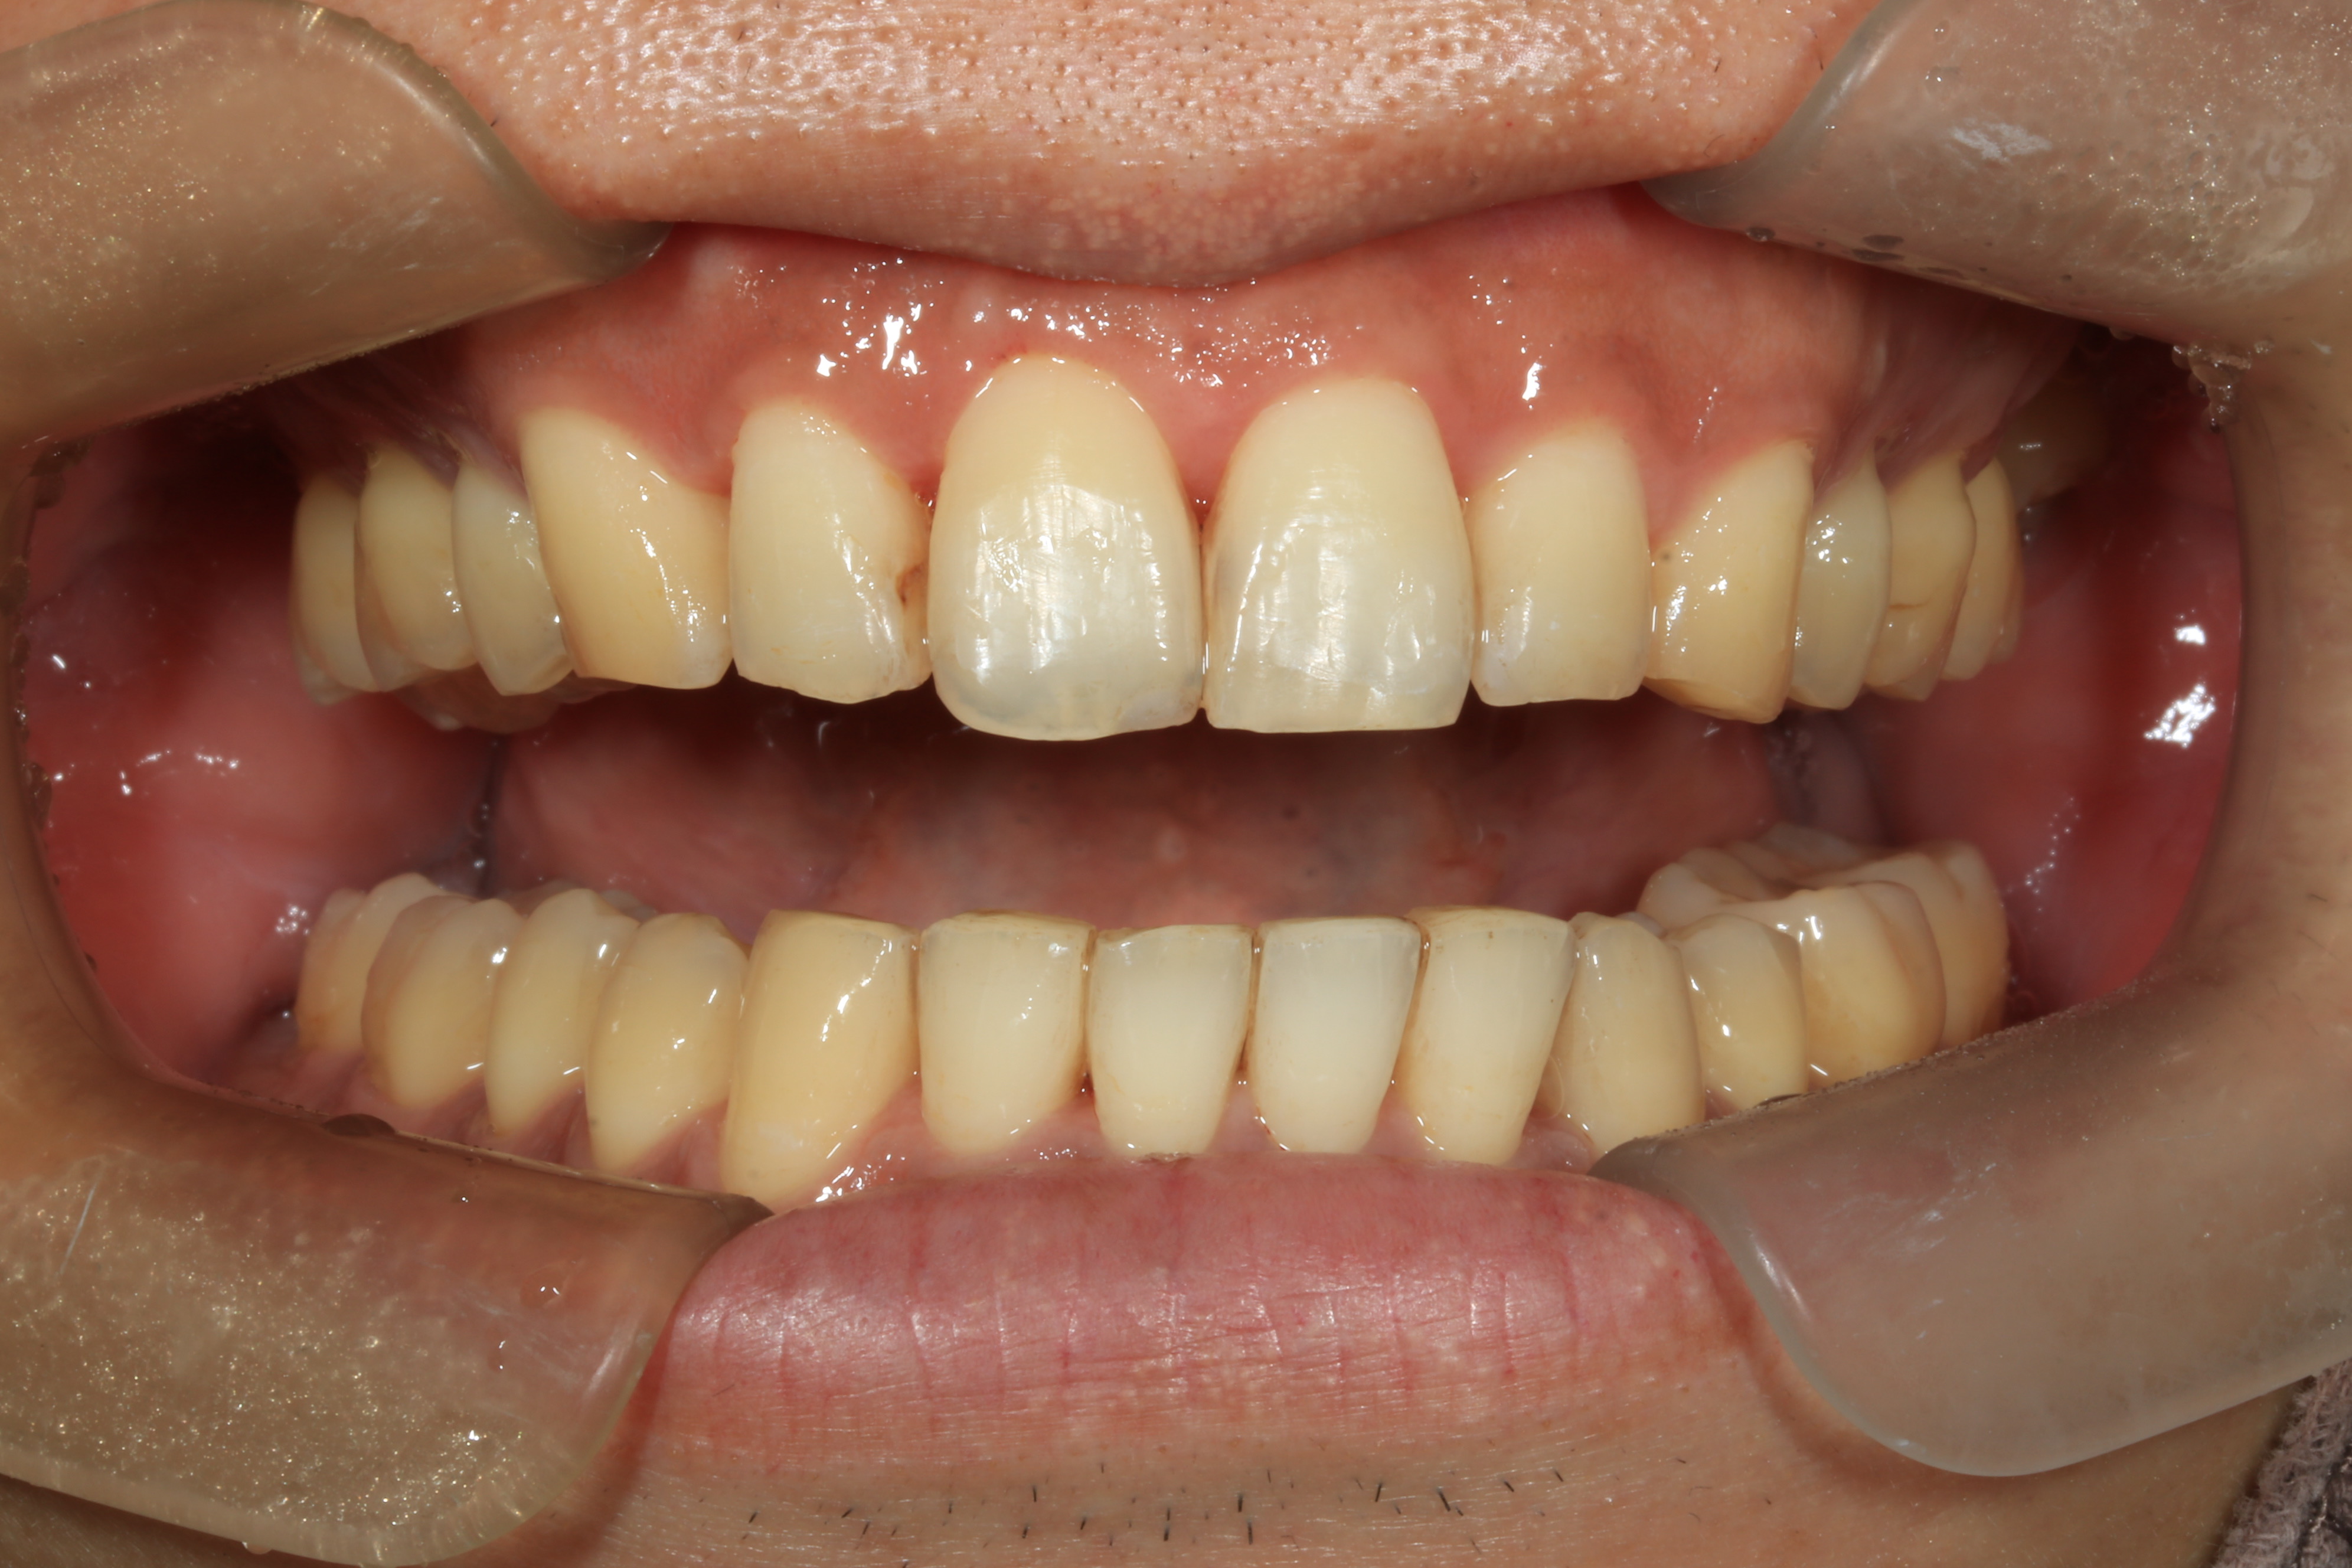

症例③

症例3_治療前 症例3_治療後

治療方法 マウスピース矯正

治療期間 1年8ヶ月

治療総額 850,000円

特記事項 抜歯なし

リスク・副作用 治療の初期段階では痛みや不快感が生じやすくなりますが、1週間前後で慣れます